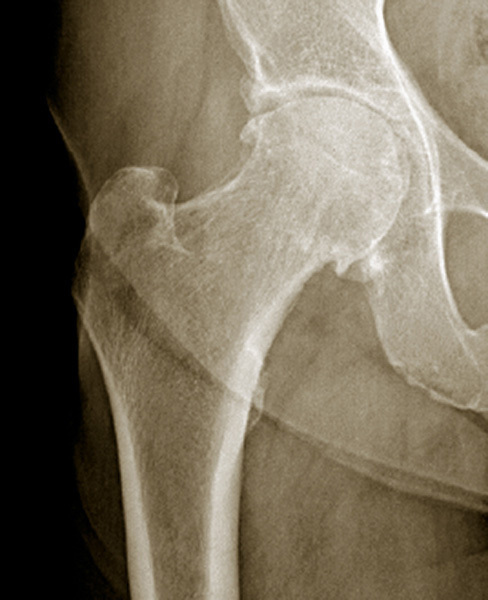

Radiographie de hanche. Coxarthrose droite évoluée ; stade 3 de Kellgren et Lawrence, pincement articulaire localisé supéro-interne, ostéophytes cotyloïdiens et péricapitaux.